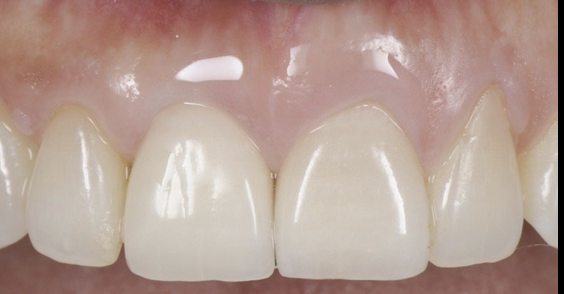

- 上顎右側前歯にインプラントを1本抜歯即時に埋入し、

- オールセラミックにて被せ物を行なった。

- 審美的な仕上がりで、患者自身も満足した。15年経過し良好である。

オールセラミックには欠け易いといったリスクがあるためナイトガードは必須である。